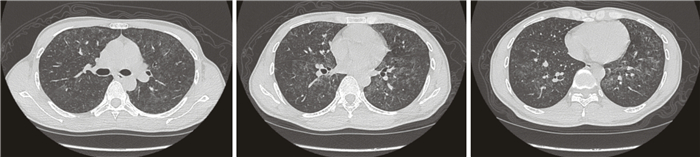

本組50例患者出現雙肺彌漫性磨玻璃影、小葉間隔增厚、網狀影結節影、肺氣囊、斑片影、碎石路征、支氣管擴張、縱隔淋巴結腫大及胸腔積液分別為100%、48%、44%、36%、30%、20%、16%、8%及4%。典型病例胸部HRCT結果見圖 3和圖 4。

以往研究表明影像學檢查在AIDS合并PCP的診斷中具有不可低估的作用[12-15]。PCP典型胸部HRCT表現為兩側肺門周圍對稱性的磨玻璃影,由肺門向外周肺野發展并有融合的趨勢。可伴有不同程度的網狀影或有小葉間隔增厚,形成“鋪路石征”,可伴有縱隔淋巴結腫大,部分可見肺氣囊、少量胸腔積液、牽拉性支氣管擴張等征象,本組50例患者出現雙肺彌漫性磨玻璃影、小葉間隔增厚、網狀影結節影及肺氣囊分別為100%、48%、44%及36%。其病理基礎是肺孢子菌侵入機體肺部,破壞Ⅰ型肺泡細胞和肺間質,出現不同程度的滲出性改變,影像學表現出磨玻璃影、網狀結節影和小葉間隔增厚影。鋪路石征是磨玻璃樣變與網狀影混合形成的影像,是增厚的肺間隔形成線狀陰影將病灶分割成多邊、不規則形,狀似鋪路石樣改變。肺氣囊是PCP的特異性影像,呈多發性,分布于胸膜近處及肺實質內,其形成與肺泡、肺間質性炎癥以及不同程度的纖維化導致肺組織重構、形成囊性病變有關。囊腫破裂可引起氣胸或縱隔皮下氣腫。一旦磨玻璃影區域內出現肺氣囊或氣胸,則強烈提示PCP。